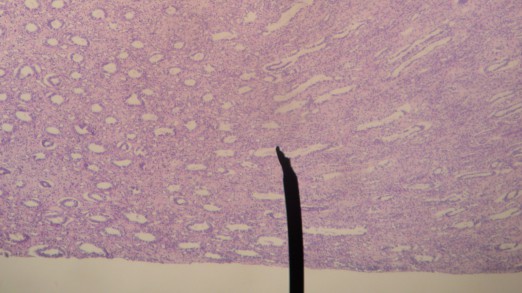

Author’ own picture. Human Kidney (Medulla). Digital camera shot through a microscope.By Jpogi at en.wikipedia (Own work Transferred from en.wikipedia) [Public domain], via Wikimedia Commons